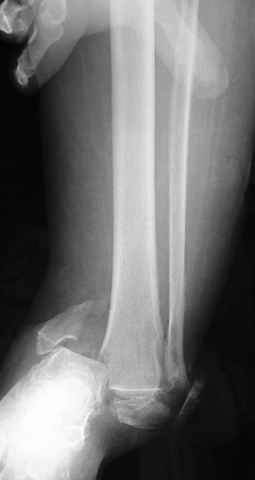

Pilon fracture:

-Появляется ориентир и остов, на чем можно строить восстановление, почему сперва малоберцовую, впервые обьяснили и описали (Pylon type and Ankle fractures) в середине 50х Rienau и Gay.

Восстановливая длину и ротацию малоберцовой кости, затем относительно легче произвести реставрацию остальных элементов перелома дистального эпиметафиза болшеберцовой кости.

первую очередь, затем остальных элементов - стал классическим при лечении данной патолгии. Латеральная колонна (столб), дистальный

конец малоберцевой кости, к нему прикрепляется латеральный суставной фрагмент дистального эпиметафиза большеберцовой кости (как на снимке)

и таранная кость, которые при репозиции малоберцовой кости репонируются автоматически.